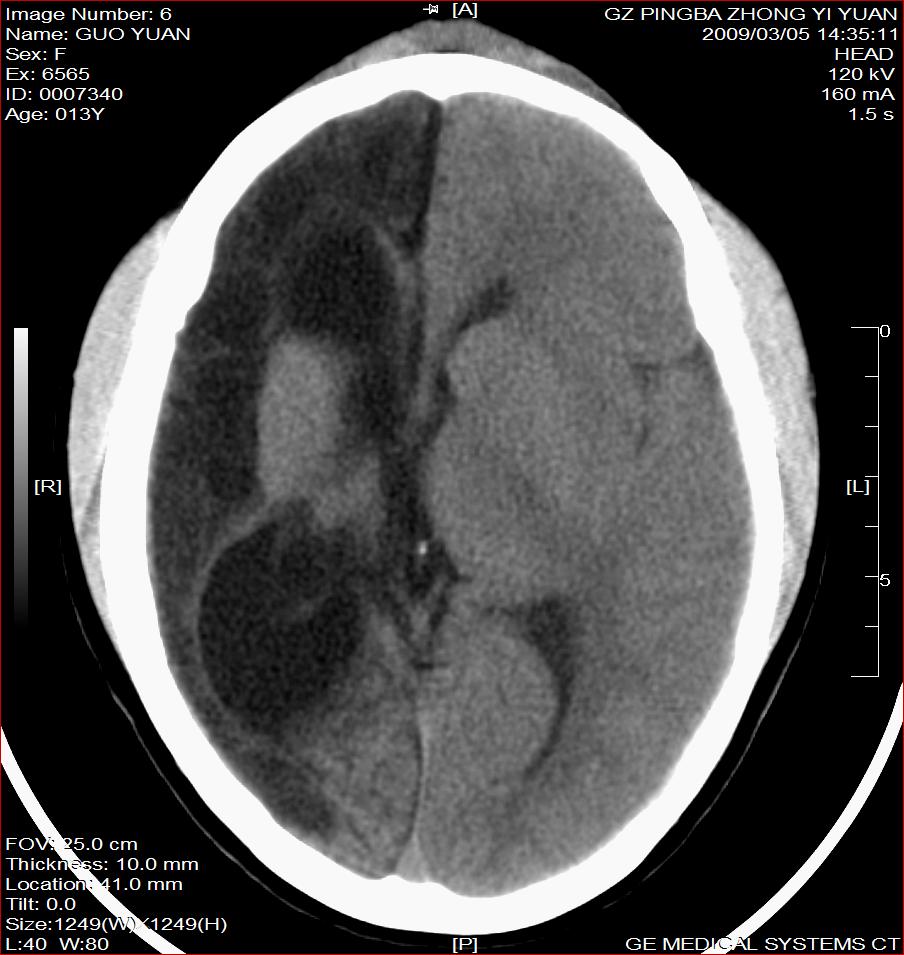

以下是引用杀毒软件在2009-3-6 17:32:00的发言:[br]右侧额颞顶部脑沟裂增宽,颞顶部楔形稍低密度影,侧脑室体部明显增宽,余脑实质内未见异常,中线结构居中。[br][br]考虑---右侧大脑半球发育不良并脑沟裂发育畸型可能性大

以下是引用随光逐影在2009-3-6 18:35:00的发言:[br]1)考虑右侧幕上半球发育不良并脑软化灶。2)双侧额部头皮软组织肿胀。